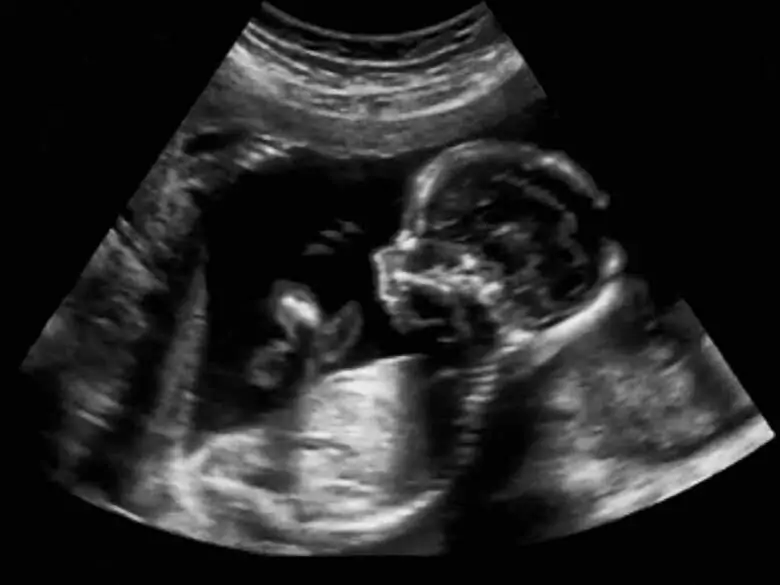

Pränatale Tests spielen seit langem eine wichtige Rolle in der Gynäkologie und Geburtshilfe. Heutzutage nimmt ihr Wert jedoch ständig zu, da immer mehr Frauen erst spät schwanger werden. Bei den pränatalen Tests wird zwischen invasiven und völlig nicht-invasiven Tests unterschieden - welche Tests werden bei der Pränataldiagnostik genau durchgeführt und wann werden diese jeweils eingesetzt?